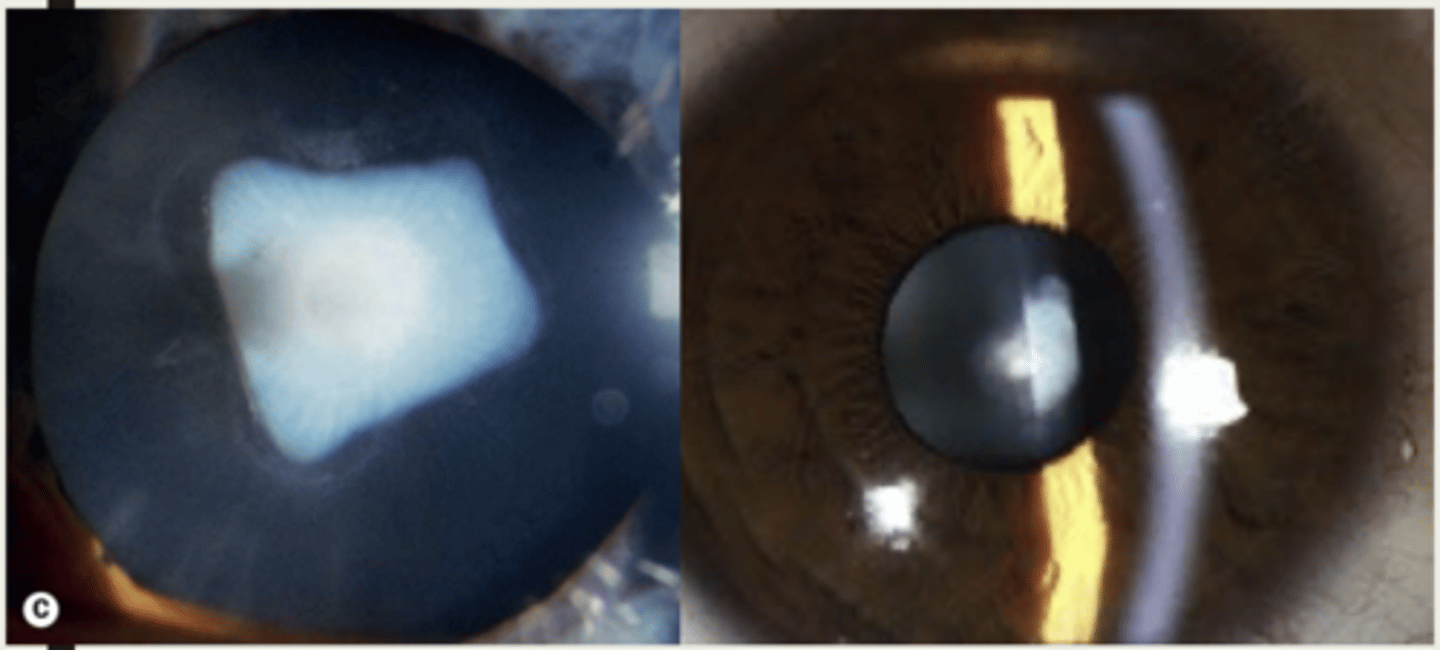

What is the presentation of a snowflake cataract?

1. grey-white branching opacities in snowflake appearance

2. eventually entire lens will turn white

What layer of the lens do snowflake cataracts start to develop in?

subcapsular (posterior subcapsular)